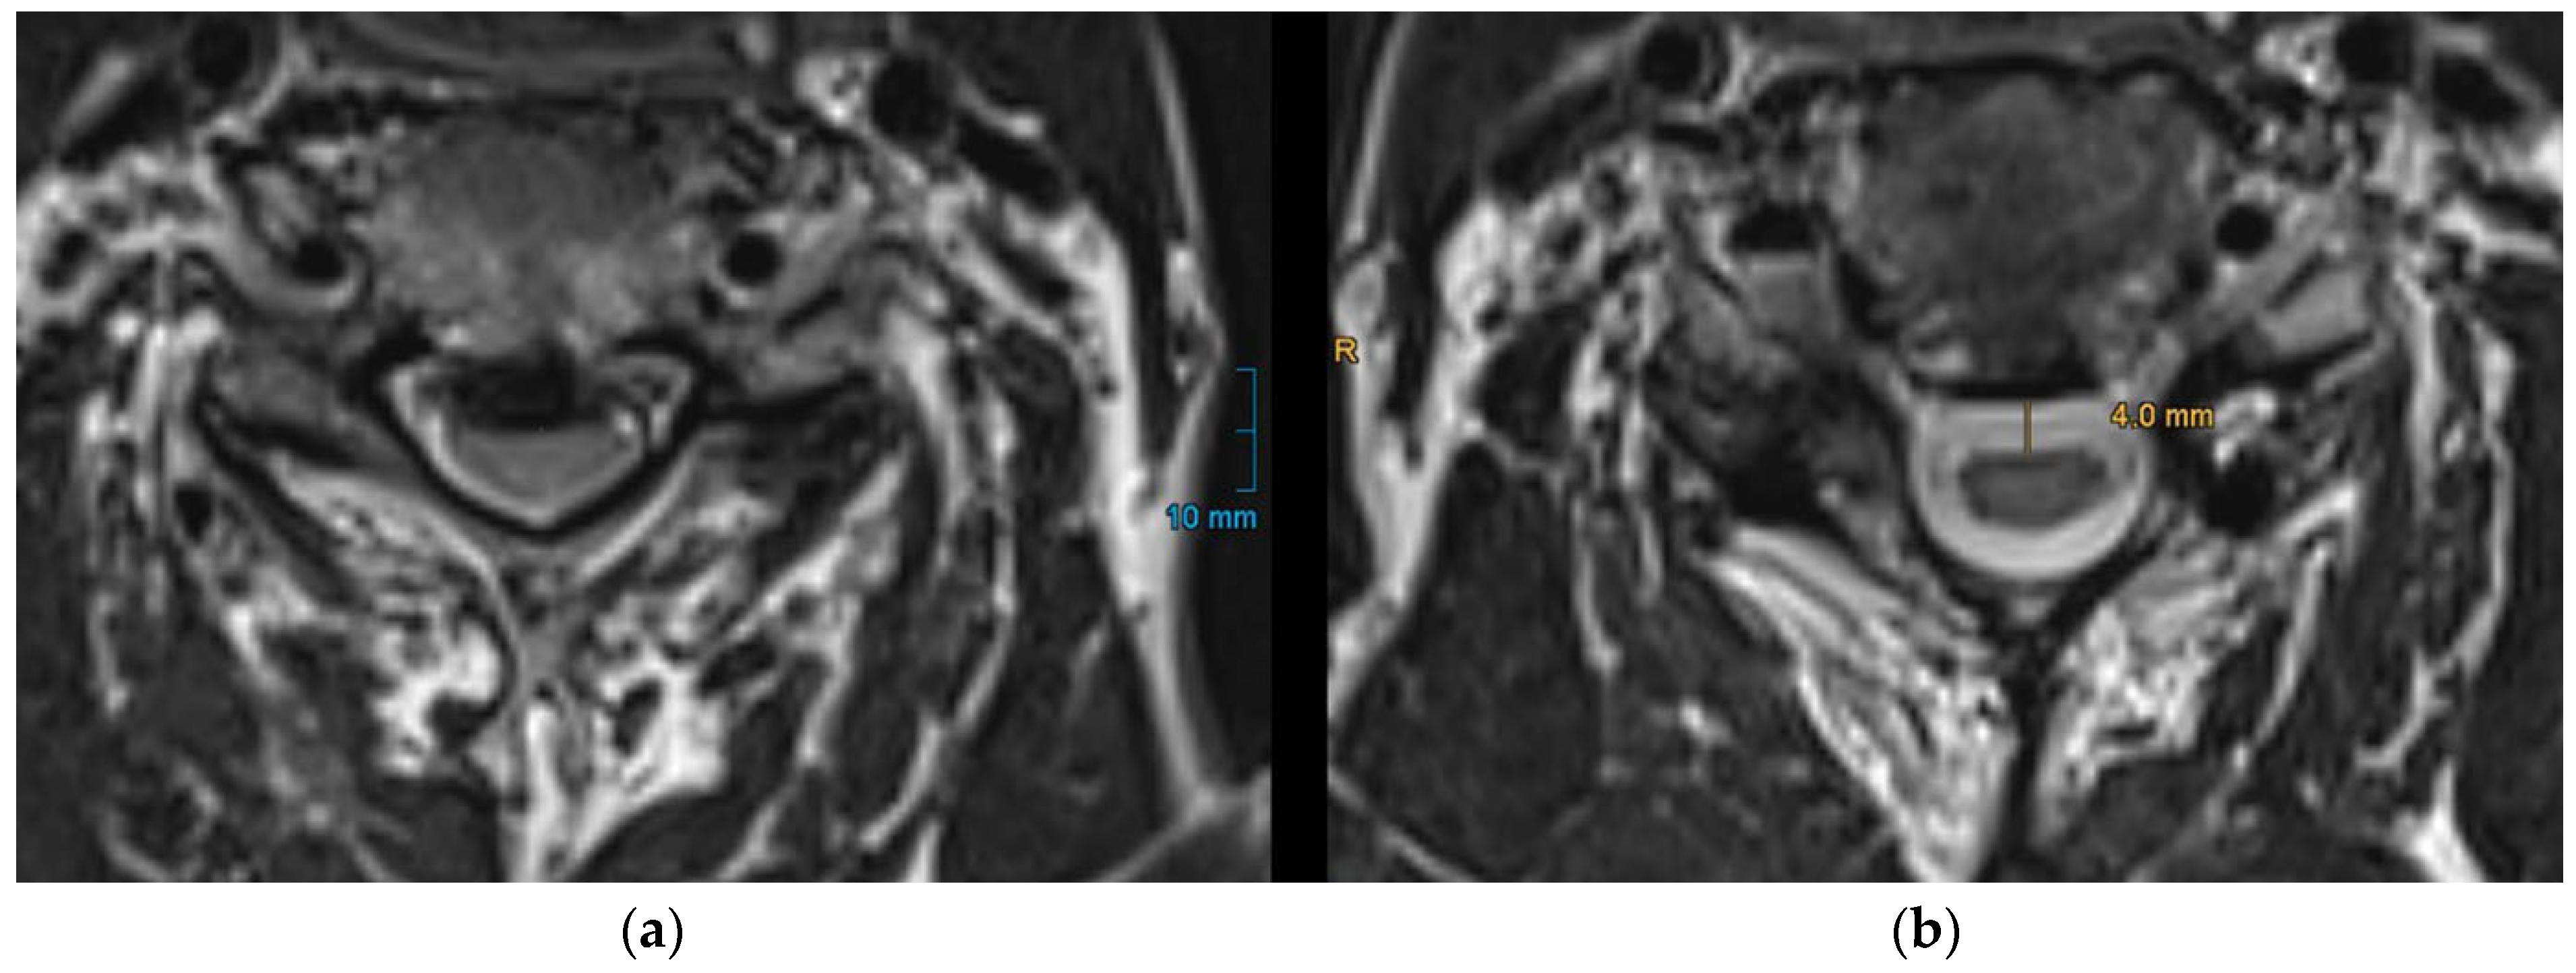

PSS was quantified by measuring the perpendicular distance from the approximated anterior limitation of the spinal cord to the anterior spinal canal (Figure 2) as it is already described in previous studies [15,18]. For patients with multilevel stenosis, this measurement was performed at each narrowed segment, and the mean PSS was calculated. To ensure measurement reliability, two independent observers (a senior and a junior spine surgeon) performed the measurements for all patients. Inter-rater reliability was assessed using intraclass correlation coefficient (ICC). The resulting ICC value was 0.91 (95% CI 0.86–0.95), indicating excellent agreement between raters.

Figure 2. Measurement of posterior spinal cord shifting (PSS) on axial T2-weighted MRI. PSS is defined as the distance from the approximated anterior limitation of the spinal cord to the anterior spinal canal. (a): preoperative MRI showing the spinal cord compression before surgery; (b): postoperative MRI illustrating the degree of PSS.